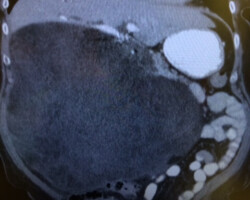

Resection of large retroperitoneal sarcoma including right and transverse colectomy and right hepatectomy